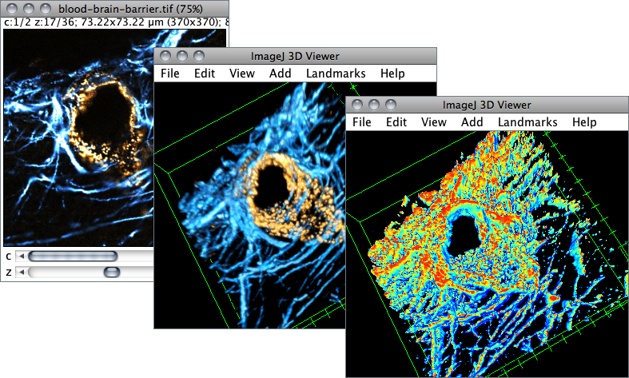

一、图片的3D可视化

通常遇到2D图片Stack,首先需要做的就是进行3D重构,以看清结构,可以使用ImageJ自带的3D可视化插件:3D Viewer(Plug

本文详细介绍了如何使用ImageJ进行3D图片的重构和体积测量。通过3D Viewer和Volume Viewer插件实现3D可视化,针对CT或MRI等Stack图像,调整Z轴步长以正确显示结构。接着,利用3D Object Counter测量3D体积和表面积,通过阈值设置和尺寸过滤确保精确测量。文章提供了详细的步骤和注意事项,适用于生物医学图像的定量分析。

本文详细介绍了如何使用ImageJ进行3D图片的重构和体积测量。通过3D Viewer和Volume Viewer插件实现3D可视化,针对CT或MRI等Stack图像,调整Z轴步长以正确显示结构。接着,利用3D Object Counter测量3D体积和表面积,通过阈值设置和尺寸过滤确保精确测量。文章提供了详细的步骤和注意事项,适用于生物医学图像的定量分析。